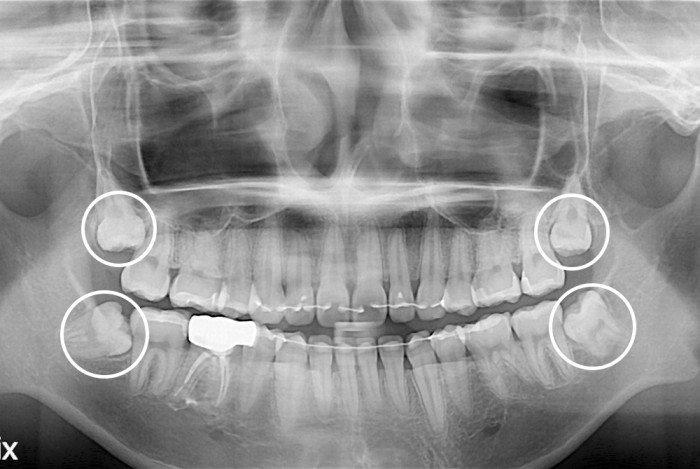

[사랑니] 사랑니

PX20200122_183413_0182_00000000.jpg

치료전 : 2020-01-22